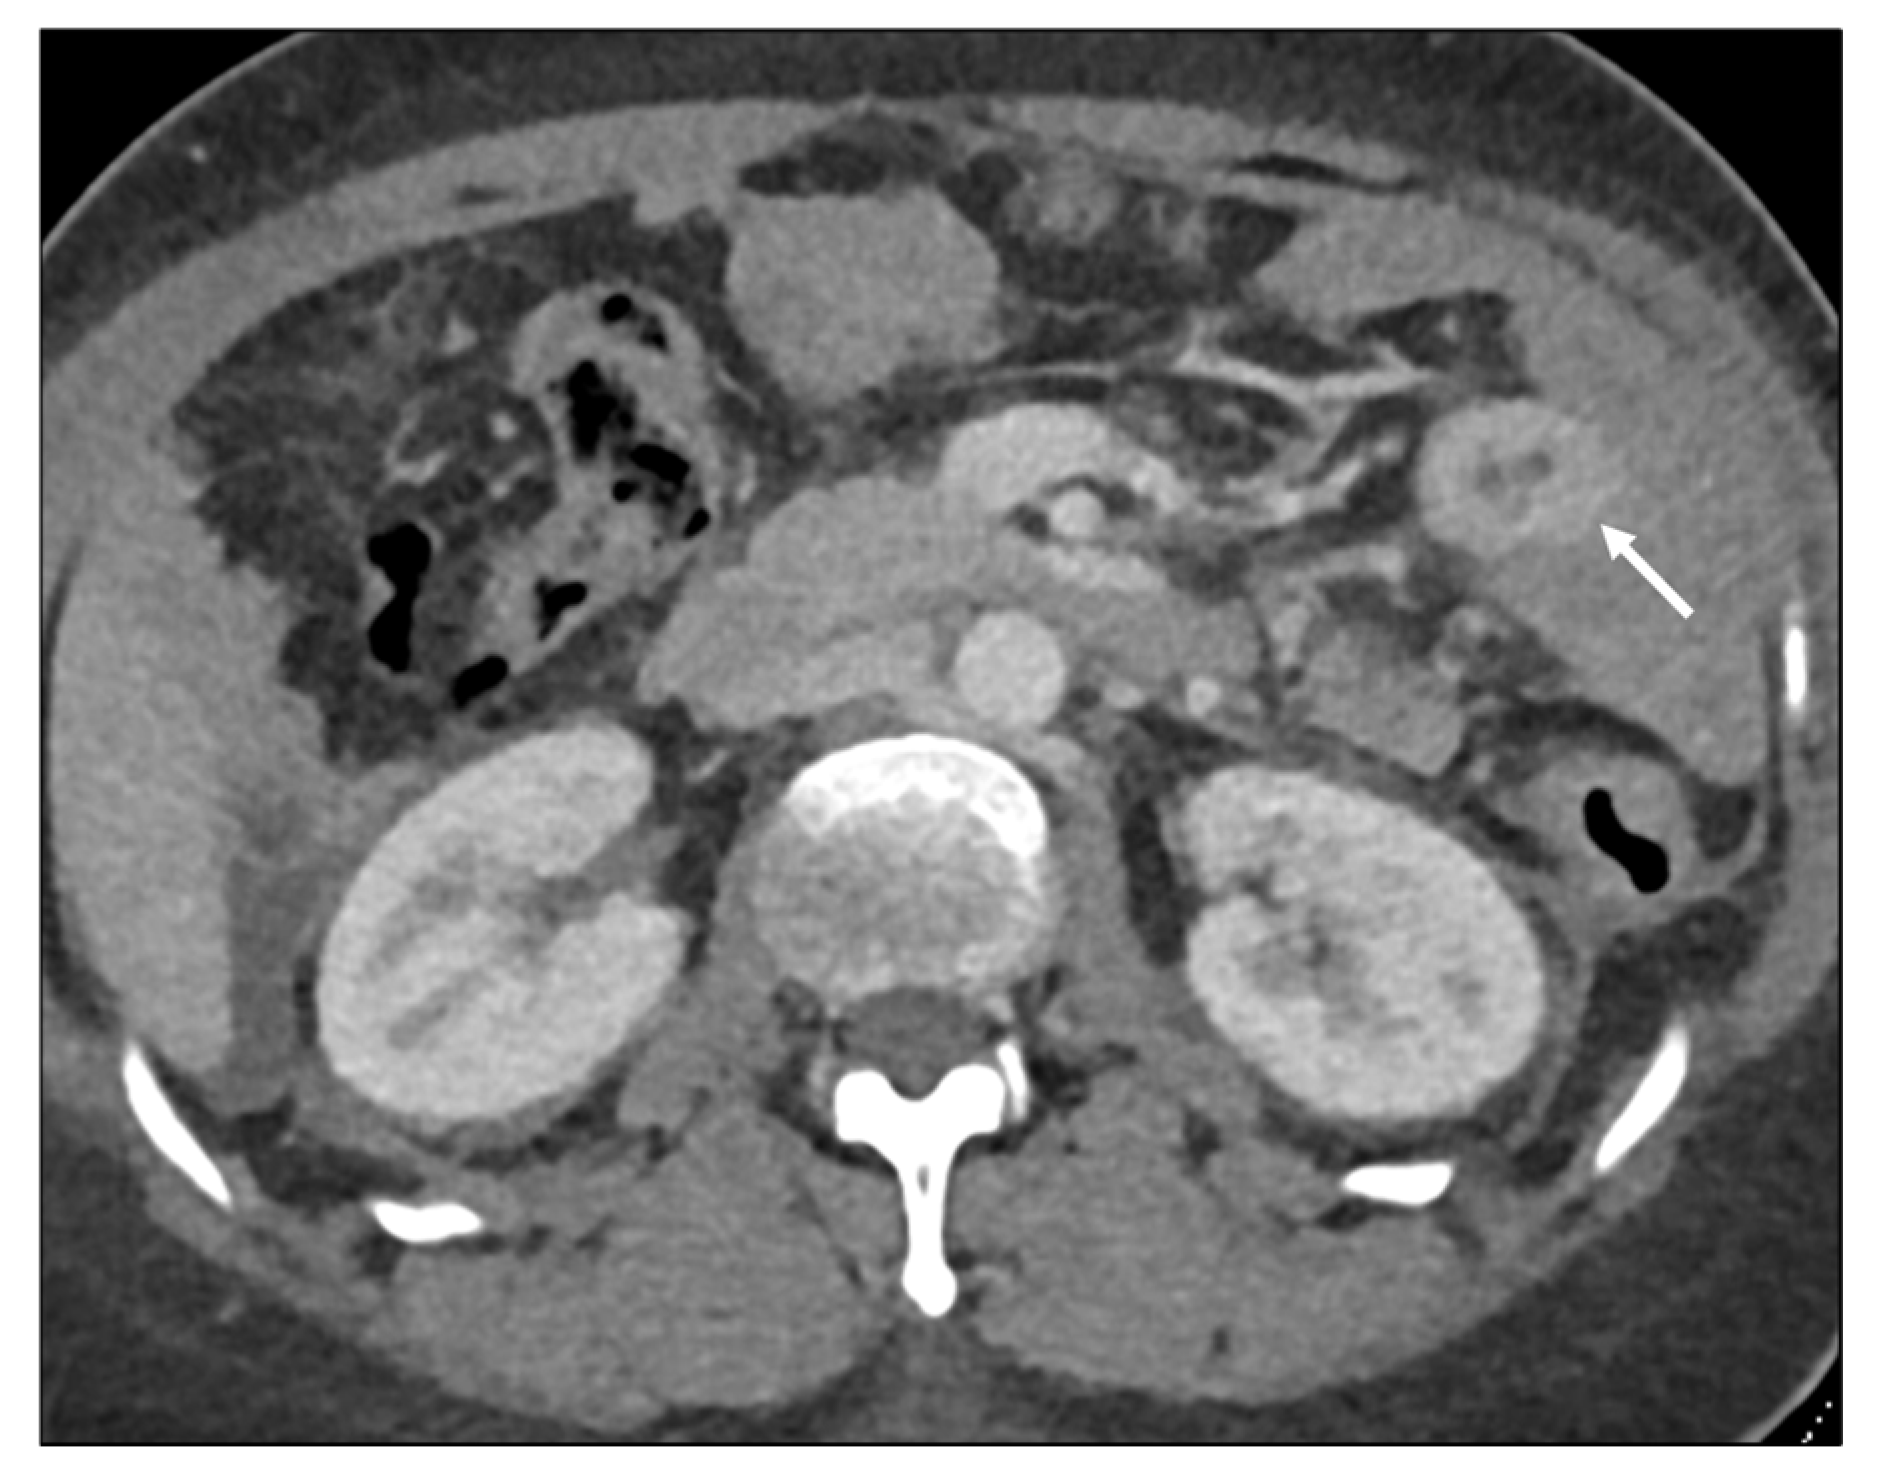

Length

- Jang, H.J.; Lim, H.K.; Kim, H.S.; Cho, E.Y.; Lee, S.J.; Kim, K.A.; Choi, D. Intestinal metastases from gastric adenocarcinoma: Helical CT findings. J. Comput. Assist. Tomogr. 2001, 25, 61–67. [Google Scholar] [CrossRef]

- Burgain, C.; Germain, A.; Bastien, C.; Orry, X.; Choné, L.; Claudon, M.; Laurent, V. Computed tomography features of gastrointestinal linitis plastica: Spectrum of findings in early and delayed phase imaging. Abdom. Radiol. 2016, 41, 1370–1377. [Google Scholar] [CrossRef]

- Macari, M.; Megibow, A.J.; Balthazar, E.J. A pattern approach to the abnormal small bowel: Observations at MDCT and CT enterography. AJR Am. J. Roentgenol. 2007, 188, 1344–1355. [Google Scholar] [CrossRef]